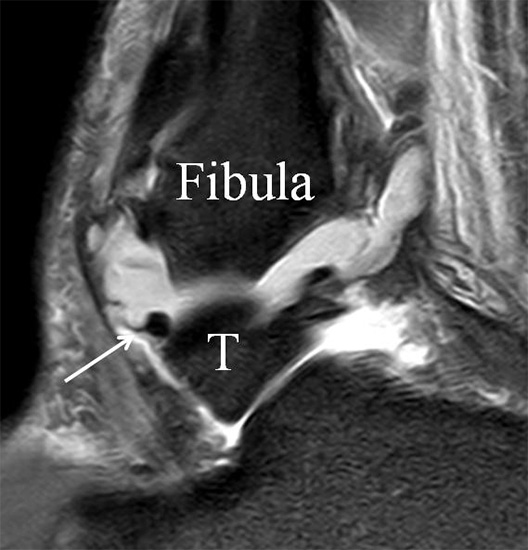

Das Ligamentum fibulotalare anterius entspricht einer bifaszikulären Struktur (Abb. 2 a) mit interponierendem fibrovaskulärem Gewebe (S. K. Sarrafian (ed). 2003). Es gibt jedoch Variationen der Ligamentanatomie. In 55% liegt das LFTA als bifaszikuläres Band (Abb. 2 a), in 9% als monofaszikuläre Bandstruktur (Abb. 2 b) und in 36% als multifaszikuläre, striäre Variante (Abb. 2 c) vor 3.

PD fs HR axial. Klare Darstellung eines filigranen, knapp über 1 mm breiten LFTA (Pfeil). Fibula (F).

Abbildung 3

Das LFTA verbindet die antero-inferiore Fibulaspitze mit dem Processus lateralis tali und inseriert hier an einem oder zwei kleinen Tuberkeln 3. Der in Neutralposition horizontale Verlauf erleichtert die kernspintomographische Darstellung in dieser Standardebene. Das LFTA weist durchschnittlich eine Breite von knapp über 2 mm auf 4. Somit sind bei einer Routinedarstellung in 3 mm Schichtdicke Anschnittsphänomene, die die Diagnostik erschweren, regelmäßig anzutreffen. Dementsprechend sind auch die ligamentären Subfaszikel nicht zu differenzieren. In koronarer Darstellung ist dies aufgrund der hohen Auflösung in der Schichtebene jedoch möglich (Abb. 2 a-c), wobei hier wiederum eine Integritätsbeurteilung des Bandes erschwert ist. Unter Verwendung hochauflösender Techniken im Millimeterbereich (Schichtdicke) sind hingegen auch in der axialen Ebene die subfaszikulären Strukturen zu beurteilen (Abb. 3).